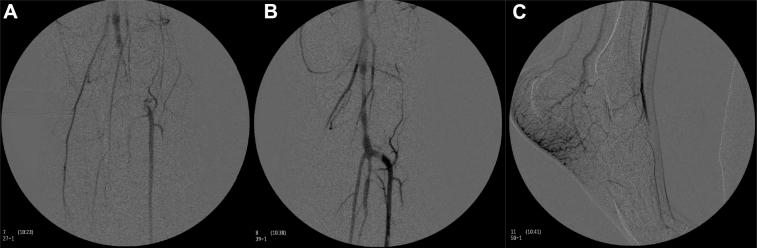

Mortality after gunshot wounds to the thoracic aorta ranges from 92% to 100%. Survival is almost always in patients with injury from low-caliber, low-velocity bullets with hemorrhage contained by the wall of the aorta. Bullet embolization, even rarer with a reported incidence of 0.3% of vascular injuries, is most commonly found during autopsy. We report the successful treatment and survival of a patient who presented with a large-caliber gunshot wound to the aortic arch with contained rupture and bullet embolization from the aortic arch to the superficial femoral artery. The patient remained functionally independent and was discharged without complication.

胸主动脉枪伤后的死亡率在92%至100%之间。存活的几乎都是那些因低口径、低速子弹致伤且主动脉壁限制出血的患者。子弹栓塞极为罕见,据报道在血管损伤中发生率为0.3%,最常见于尸检时发现。我们报告了一名患者的成功治疗及存活情况,该患者因大口径子弹枪伤主动脉弓,伴有主动脉弓破裂及子弹从主动脉弓栓塞至股浅动脉。患者出院时功能独立,无并发症。